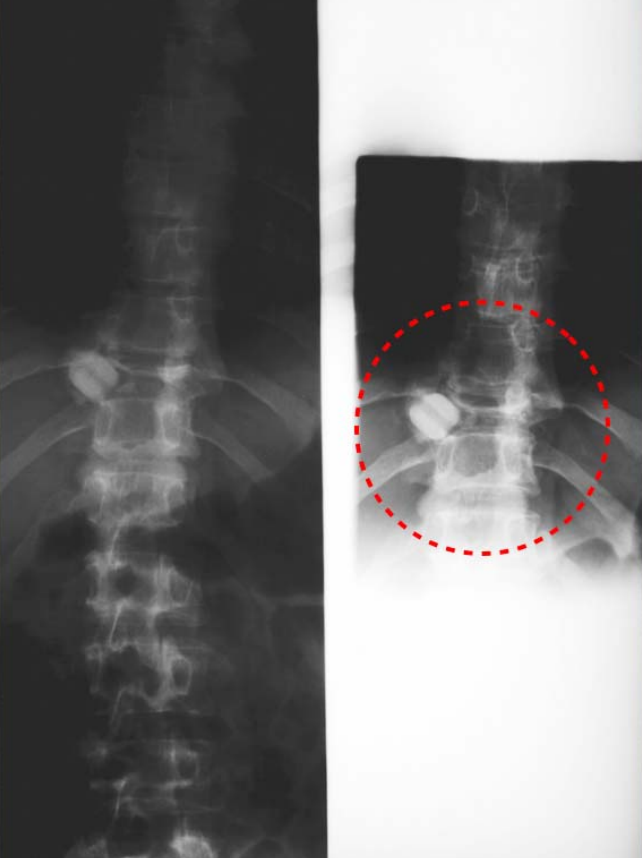

Figure2